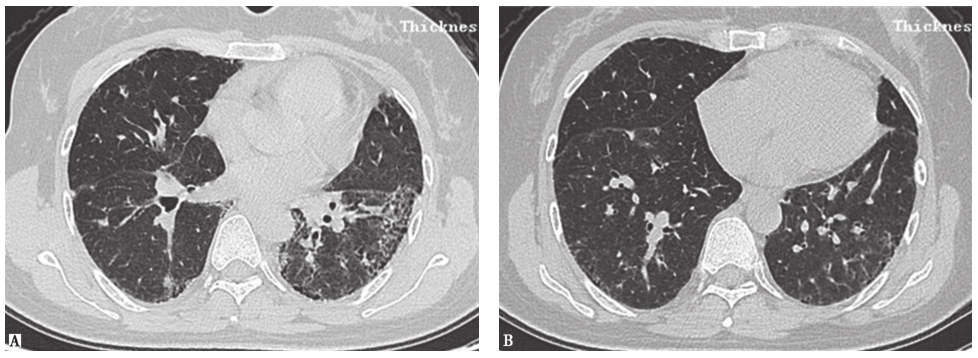

外院胸部CT示两肺散在磨玻璃影、弥漫性小结节影(图1),局部可见牵拉性支气管扩张。

图1外院胸部CT表现

两肺散在磨玻璃影及小结节影(图13),局部网状影,较入院前(图1)明显吸收、好转。

图13入院后胸部HRCT表现

患者入院后所做系列检查显示:①自身抗体均阴性,结合临床表现,基本可排除风湿免疫病;②常规病原学检查均阴性;③胸部HRCT可见两肺小结节影、磨玻璃影,较外院CT明显吸收、好转,证明外院激素治疗有效。此外,患者在未接受抗肿瘤治疗的情况下小结节影吸收、好转,与肺转移癌不符(由于癌细胞不断增殖,粟粒状癌灶可在短时间内渐进性增大)。